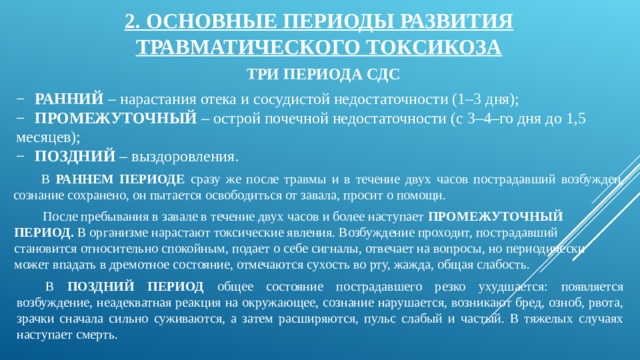

Классификация синдрома длительного раздавливания: основные категории и признаки